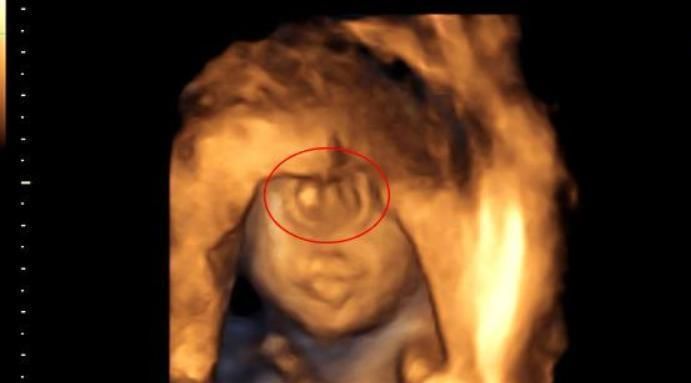

胎儿哪种情况产检检查不出来?

1、视力异常

像李女士宝宝的情况,就属于先天性的视力异常,而且大部分无法治愈。因为胎儿在腹中时,不会睁开眼睛,出生后也需要一段时间睁开眼睛,所以,宝宝的视力问题,只能通过后天检查。

有调查显示,0到10岁的孩子,如果视力有问题,一半以上都是天生的,因为产检无法检测宝宝的眼球是否正常,无论是B超还是核磁都不行。

3、指端异常

简单说就是宝宝多指缺指的问题,原则上宝宝如果有指端异常的问题,做B超是能看出来的,但现实中的B超清晰度太低,如果宝宝是握拳的姿势,根本看不到他们的手指和脚趾,就算是三维和四维也不行。